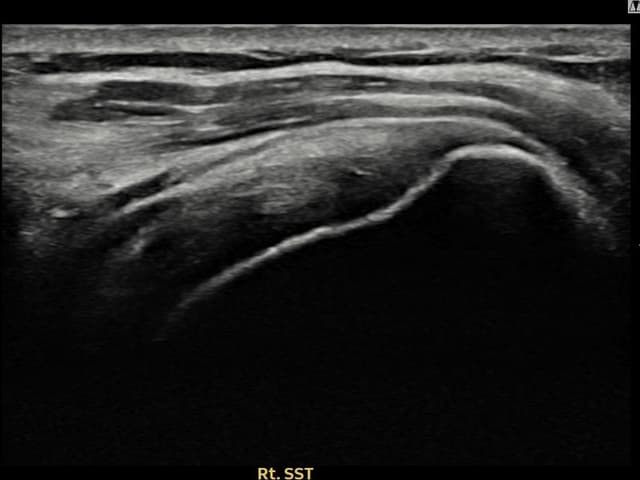

[経過期間: 23.09.01~23.11.03]

[縫縮術] 超音波検査にて右 棘上筋腱 滑液包面側部分断裂(8mm × 4mm (腱厚の約35%欠損))を確認。縫縮術施行後、腱の連続性が回復し、日常生活に復帰されました。